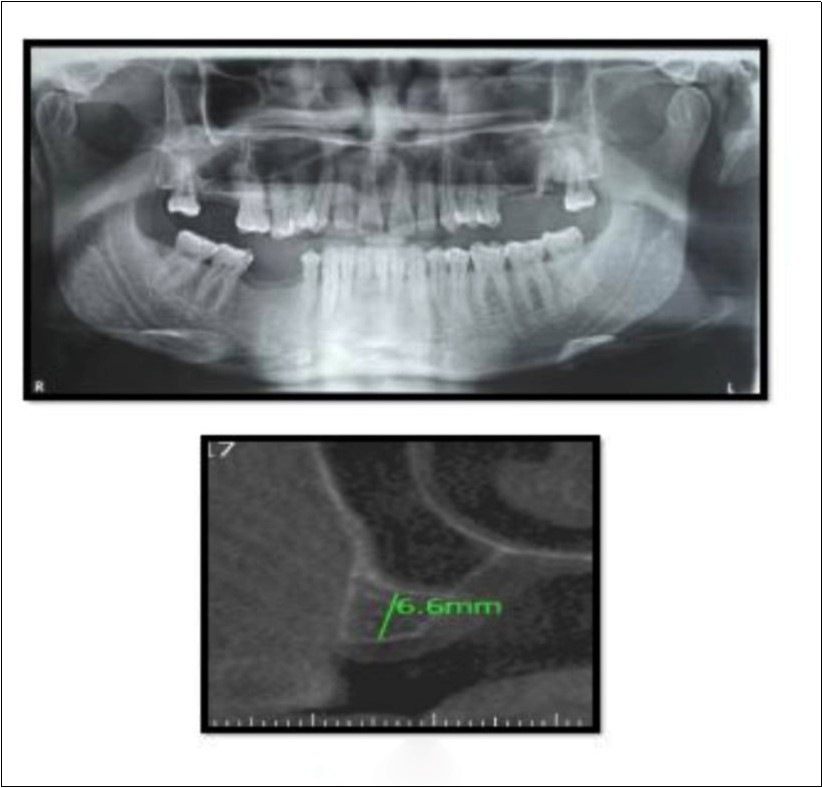

Case Report 2

A 45 year old patient with a residual bone height of 6.6 mm in 17 region underwent procedure of indirect sinus elevation using sinus osteotomy in relation to 17 region. Synthetic graft material was dispensed through the crestal osteotomy site to maintain the elevated sinus membrane followed by placement of a dental implant measuring 5 mm x 10 mm under local anesthesia and strict aseptic protocols. The implant was allowed to osseo-integrate for a period of six months during which the patient was followed periodically and was assessed for peri-implantitis, crestal bone loss and mobility. At the end of 6 months, a CBCT scan was advised to evaluate the increase in bone height which was 12mm. (Figure 3, Figure 4)

Figure 3.Pre-operative Orthopantomograph and cross section of CBCT showing residual alveolar bone height

Figure 4.Post-operative Orthopantomograph and cross section of CBCT showing residual alveolar bone height